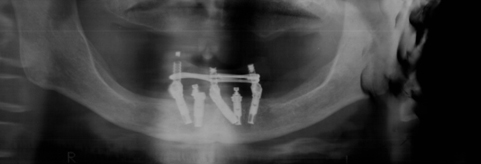

手術後

インプラントを5本入れ当日に仮歯を入れました。仮歯に穴をあけスクリューでインプラント体と固定します。こうすることにより動かない仮歯が作れます。